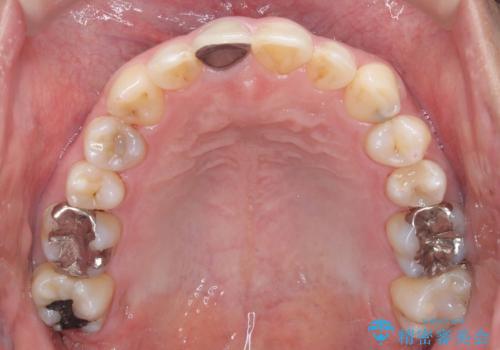

【インビザライン】八重歯と歯のでこぼこが気になる!

- 「八重歯と歯のでこぼこを治したい」を主訴に来院された患者様です。

歯は抜かずに奥歯の遠心移動とIPRで八重歯とでこぼこを改善しました。

左上3番は保険治療(CR)の劣化による二次カリエスになっていますので、後日治療予定です。